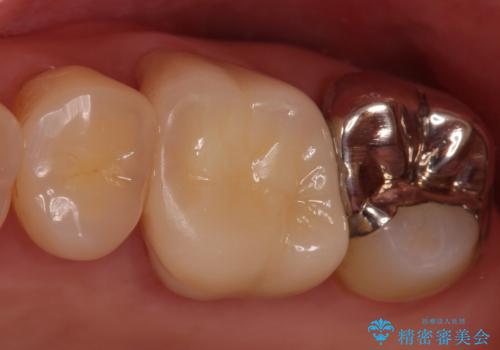

割れた被せ物を作りなおしたい

- 左上6/仮歯+ジルコニアクラウン:11,000円+110,000円費用は治療当時の料金となります

被せ物の厚みが十分に確保できていないと、材料によっては今回のように割れてしまうことがあります。

被せ物の材料を変えるか、厚みを確保することでそのリスクを抑えることができます。

今回はセラミックでの再治療をご希望されたため被せ物の厚みを確保することで対応しました。